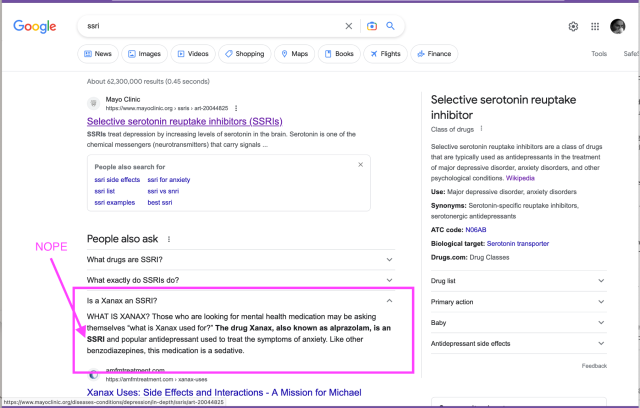

"The politics here are obvious. As Brewster Kahle put it, this decision conceives of libraries as "customer service departments for corporate database products." The truth is that libraries are ancient, bedrock institutions. Libraries are older than copyright. They're older than printing. Than paper. Than commerce."

📚 💫

@pluralistic on the @internetarchive case: